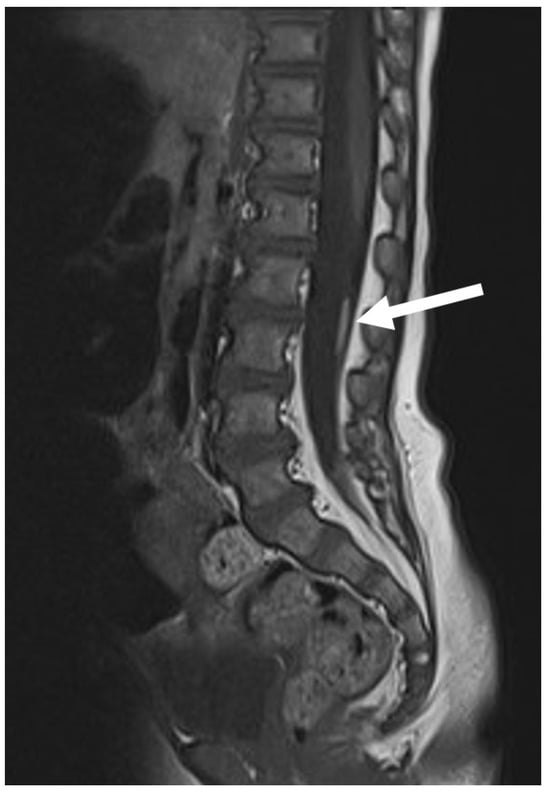

If the histological composition of the fibrous tract is predominantly neural rather than fibrous, it is better defined as LDM (Figure 8) [7]. When there is communication between the CSF and the subcutaneous compartment through the neural tract, the LDM can take on a cystic morphology. In these cases, the skin overlying the subcutaneous cyst can be very thin, so these cases may be difficult to distinguish from MMC, especially on prenatal ultrasounds. Undoubtedly, the neurological and general prognosis is much worse in MMC than in LDM.

Figure 8. LDM is formed by neural tissue that is tethered toward the extraspinal mesodermal tissues. Note the deformed dorsal aspect of the spinal cord at the level of the dysraphic lesion (white arrow), which can be located at any level of the spinal cord.